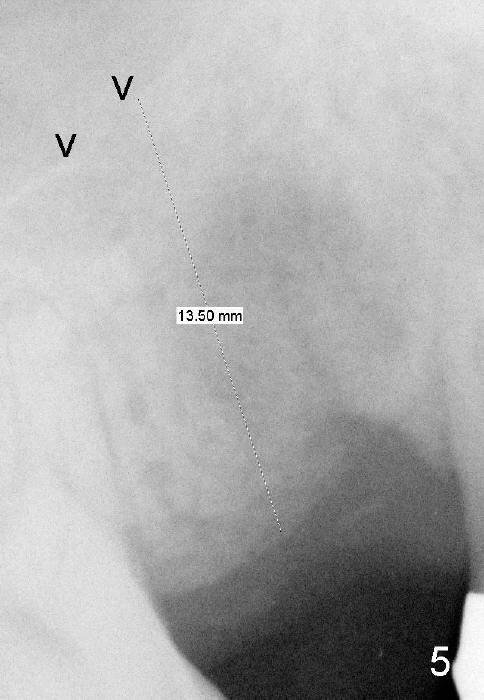

Four months after implant removal, the bony defect appears to increase (Fig.5). Reamers (Fig.6 R)and osteotome (Fig.7 O) are short of the sinus floor (arrowheads). A 5x14 mm tapered implant is placed with primary stability (Fig.8 I). The implant is placed ~ 2 mm deeper (Fig.9). No bone graft is used for sinus lift. There is no complication. The sinus floor appears to be repaired 4.5 months postop (Fig.10). Fig.11 (trimmed from panoramic X-ray) is taken 1 year 7 months post cementation. The bone remains stable 4 years 2 months post cementation (Fig.12); the mesial defect is most likely related to extraction trauma (*).